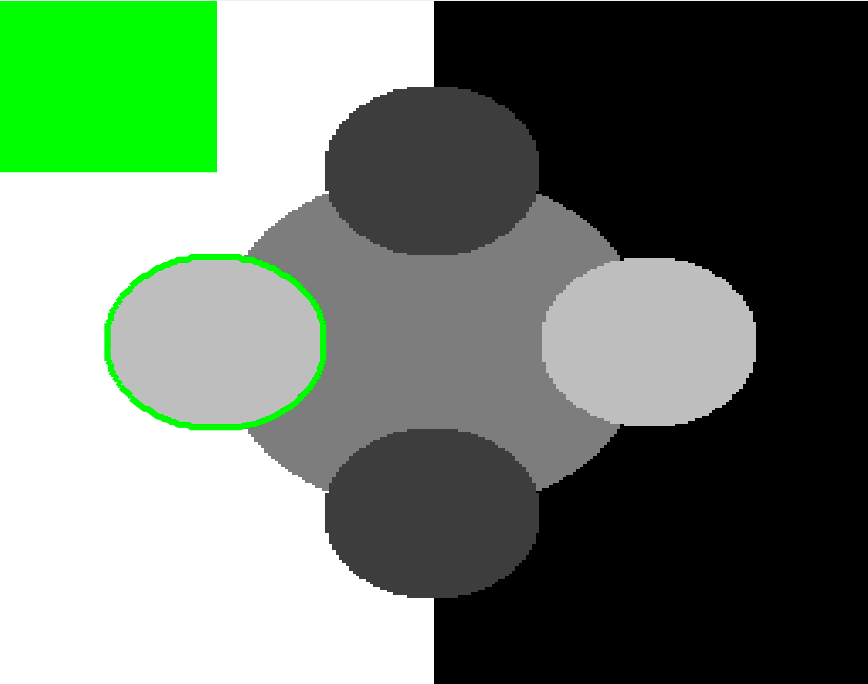

The motivation for this work comes from observing contradictions in using piecewise-constant intensity fitting terms in selective segmentation. Whilst good results are possible with this approach, the exceptional cases lead to severe limitations in practice. This is quite common in medical imaging as demonstrated in Fig. 1, where the target foreground has a low intensity. Given that the corresponding background includes large regions of low intensity, the optimal average intensities for this segmentation problem are and . For cases where , we see that by (1), almost everywhere in the domain . This means that it is very difficult to achieve an adequate result, without an over-reliance on the user input or parameter selection.

| (10) |

where is noise, is the characteristic function of the region , for respectively. The idea of selective segmentation is to incorporate user input to apply constraints that exclude regions classified as foreground, based on their location in the image. We use a distance constraint which penalises the distance from the user input markers. However, a key problem for selective segmentation is that for cases where the optimal intensity values and are similar, the intensity fitting term will become obsolete as the contour evolves. This is illustrated in Fig. 3. The purpose of our approach is to construct a model that is based on assumptions that are consistent with the observed image and any homogeneous target region of interest. A common approach in selective segmentation is to discriminate between objects of a similar intensity Rada:13 ; Geo ; CDSS . However, the fitting terms in previous formulations Klodt:13 ; Rada:13 ; Geo ; CDSS aren’t applicable in many cases as there are contradictions in the formulation in this context. We will address this in detail in the following section.

In this section we introduce the proposed data fitting term for selective segmentation. We consider objects that are approximately homogeneous in the target region. Intrinsically, it is then assumed that the region , provided by the user, is likely to provide a reasonable approximation of the optimal value and therefore an appropriate foreground fitting function, , is given by CV (2). For this reason, it makes sense to retain this term in the proposed approach. The contradiction is in how the background fitting function is defined. Considering piecewise-constant assumptions of the image, and many of the related approaches, the background is expected to be defined by a single constant value, . If then everywhere, and therefore the fitting term can’t accurately separate background regions from the foreground. It is not practical to rely on to overcome this difficulty as it will produce an over-dependence on the choice of and . This is prohibitive in practice. An alternative function must therefore be defined which is compatible with and . Here, we define a new data fitting term that penalises background objects in such a way that avoids these problems by allowing intensity variation above and below the value . In order to design a new functional, we first look at the original CV background fitting function

We define the proposed data fitting functional as follows:

for and as defined in (33). This is consistent with respect to the intensities of the observed object and the concept of selective segmentation. In Fig. 3 we see the difference between CV and the proposed fitting terms for given user input on a CT image. For the CT image, the CV fitting terms are near 0 within the target region. This is despite there being a distinct homogeneous area with good contrast on the boundary. This illustrates the problem we are aiming to overcome. With the proposed fitting term this phenomenon should be avoided in cases like this. By defining as in (33) there is no contradiction if the foreground and background intensities of the target region are similar.